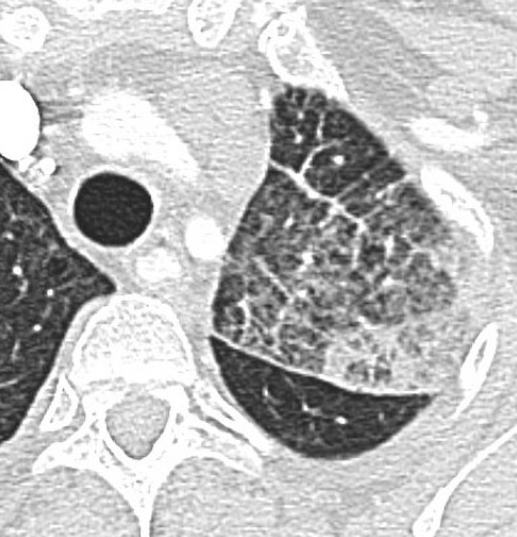

CT

- Epaississements irréguliers des septas

- Epaississements péri-bronchovasculaires